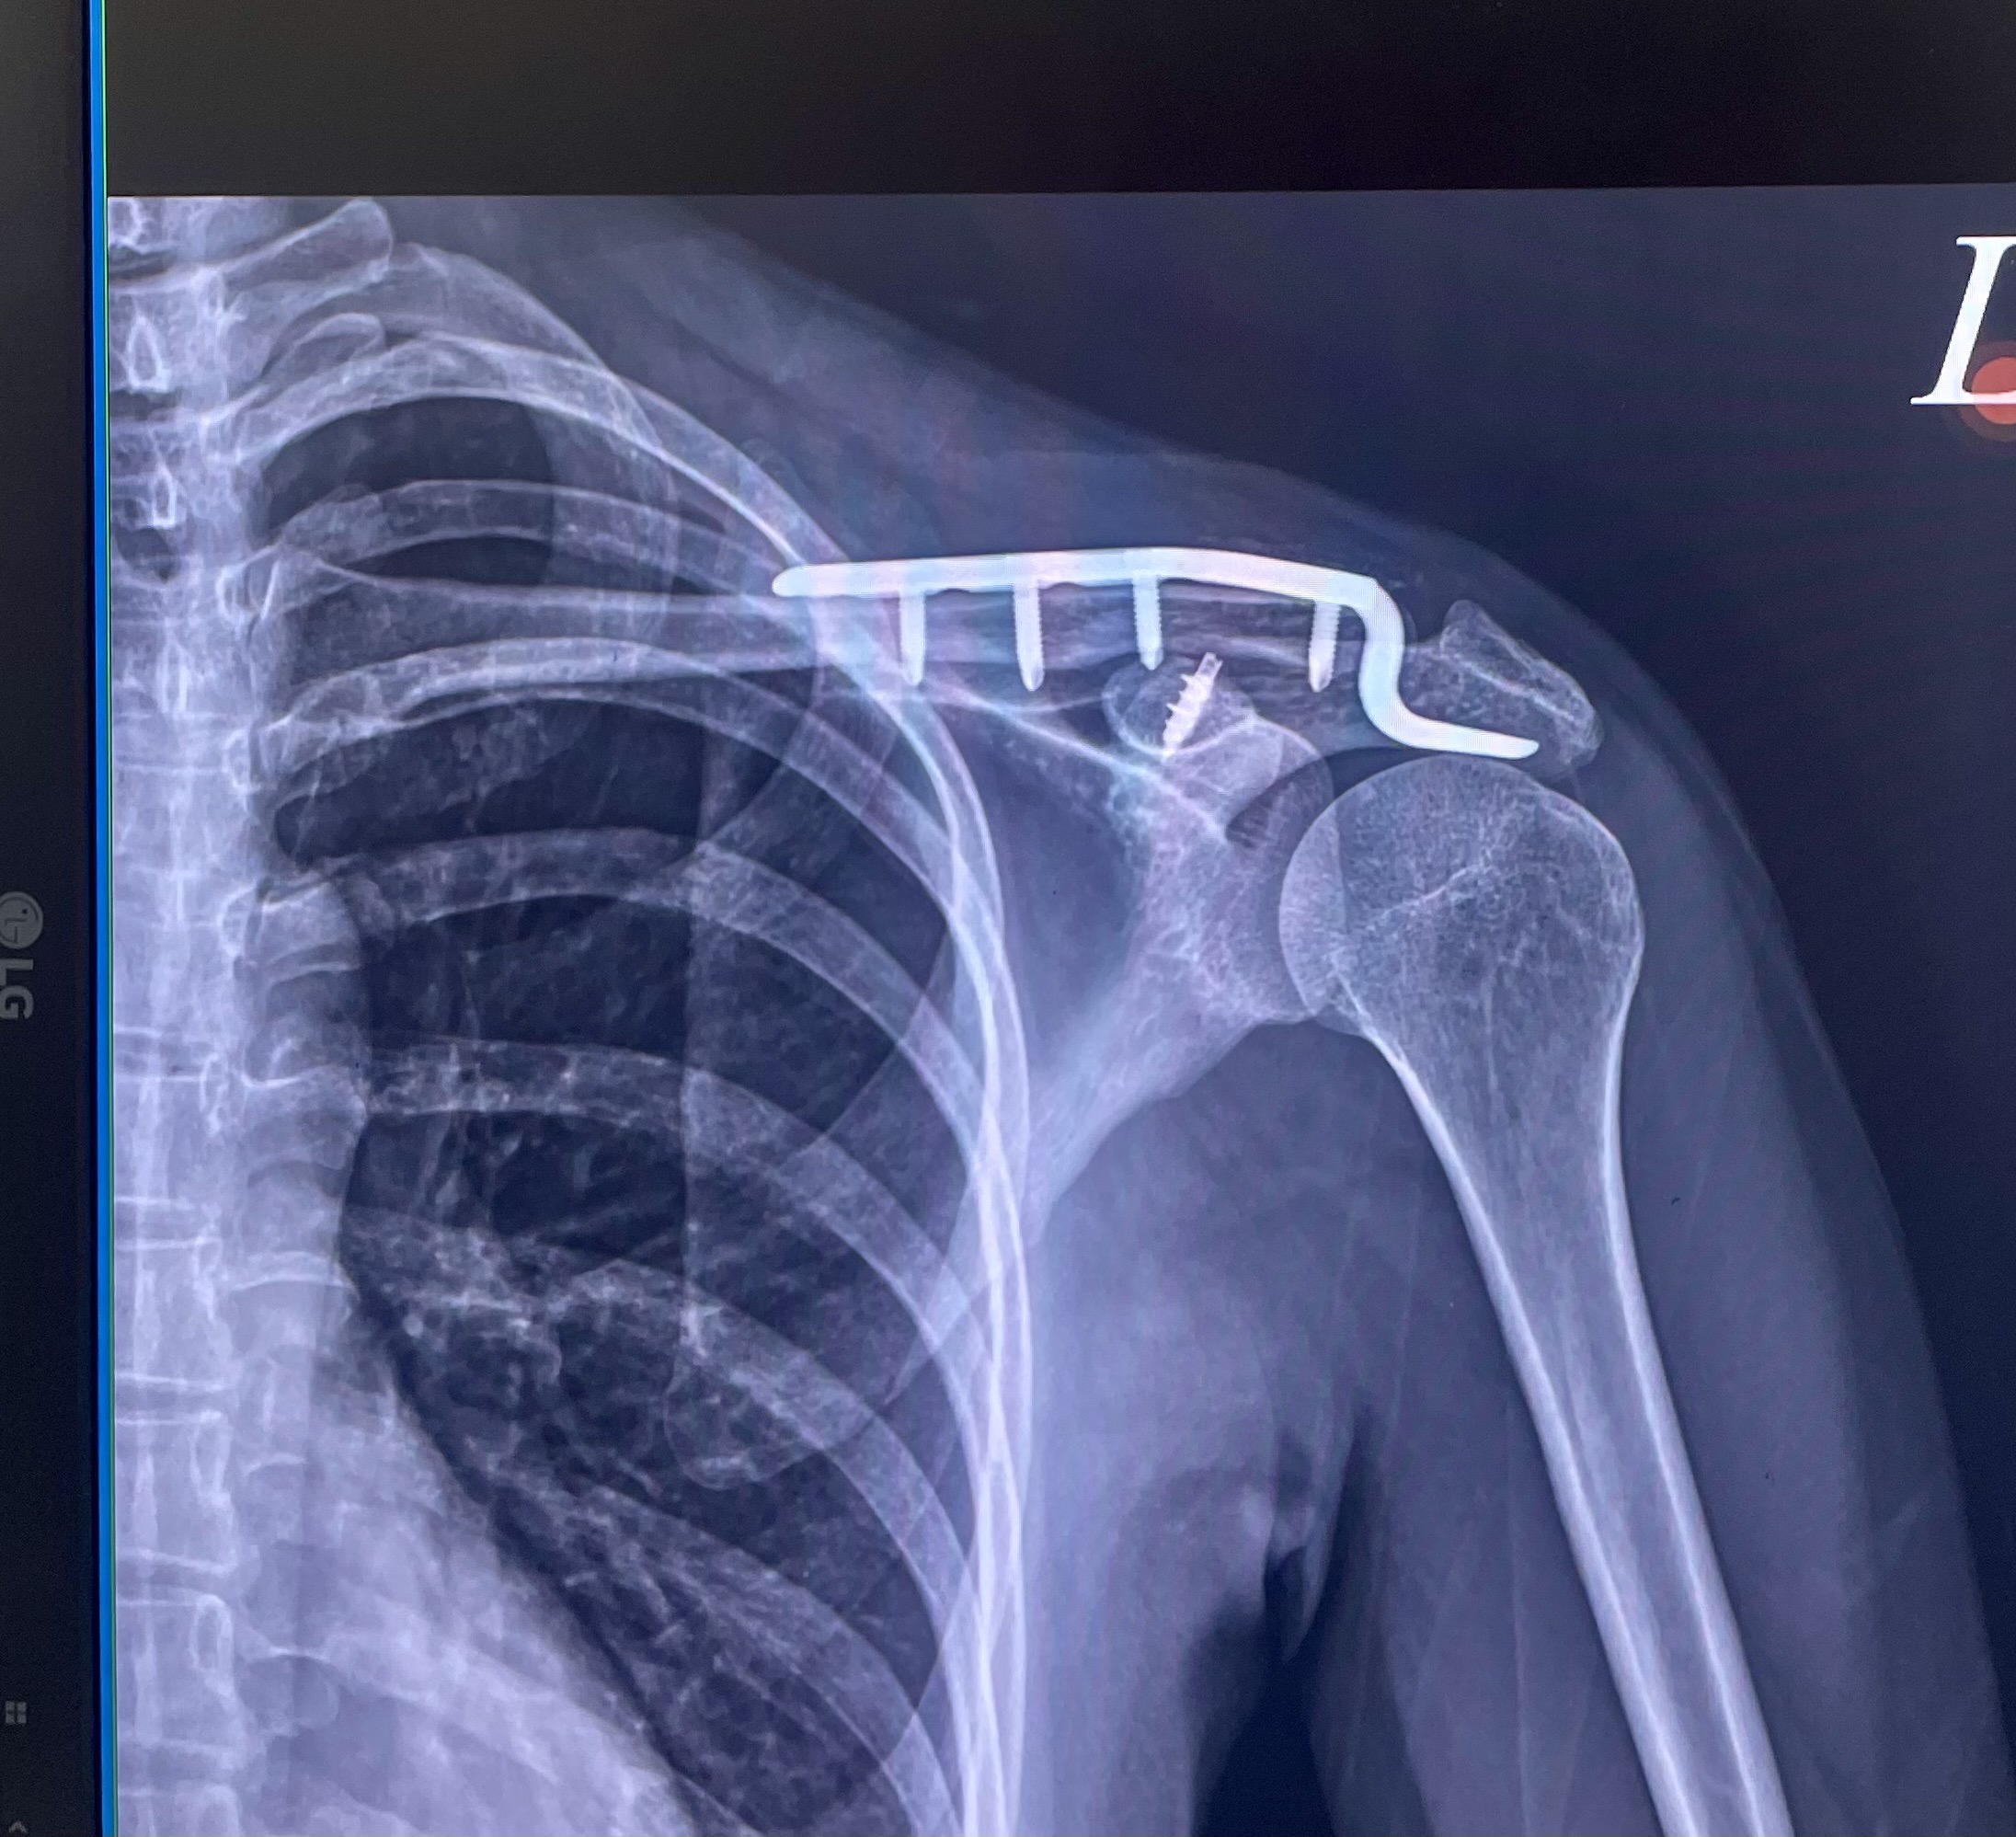

左側遠端鎖骨位移性骨折,手術植入鈦金屬骨板,恢復需一年以上

手術 左側遠端鎖骨骨手術復位併鈦合金五爪式解剖型勾行鋼板內固定

住院手術 — 鈦骨板植入(1/17-1/19) $136,154